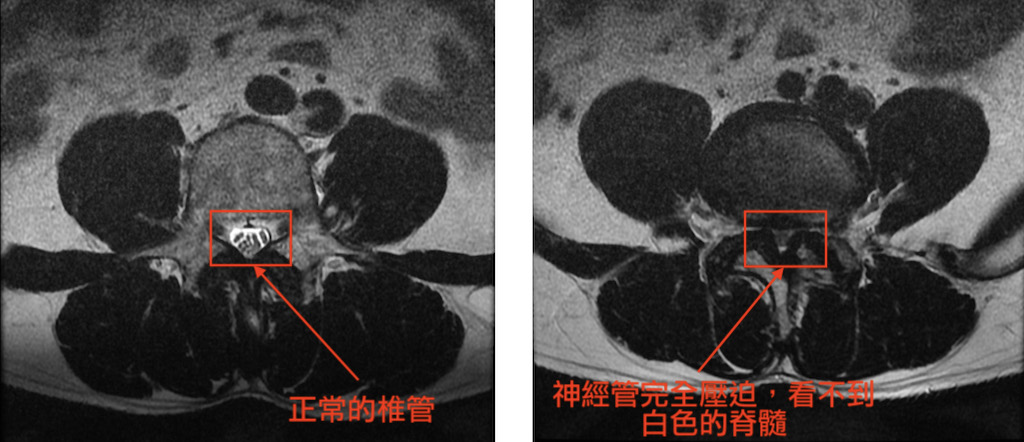

椎間管狹窄合併脊椎滑脫 用雙通道內視鏡脊椎微創手術做椎體融合術 陳奕霖醫師